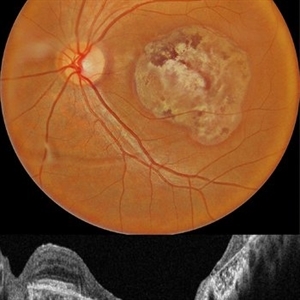

Childhood Acquired Ocular Toxoplasmosis

Childhood Acquired Ocular Toxoplasmosis

Sep 13 2023 by Deepak Bhojwani, MS

Fundus image of a 16 year old boy diaagnosed with Ocular Toxoplasmosis since the age of 10 years showing the classic toxo chorioretinitis scar on the posterior pole. Luckily the scar is loacted juxtatemporal to fovea on OCT and so the boy has good vision of 20/30.

Photographer: DR DEEPAK BHOJWANI

Imaging device: OPTCAL COHERENCE TOMOGRAPHY

Condition/keywords: posterior uveitis, toxo chorioretinitis